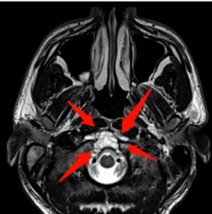

病情回顾:23岁法国小伙Lucas因右侧舌下麻痹和舌萎缩就诊,发现以颈静脉结节为中心的T2高信号和溶骨性病变(图1A和B)。

▼图1.术前MR显示以右颈静脉结节为中心病变,位于颈静脉孔内侧,考虑软骨肉瘤可能。

▼图2,术后MR证实软骨肉瘤完全切除。

▼术后影像学证实了肿瘤全切(图7C)和颈静脉孔保留通畅(图7D)。在这种情况下,神经内镜筷子技术有助于顺利合适地暴露、探查神经和斜坡旁颈内动脉,并通过有限且定制的手术入路向下到达对侧肿瘤所在位置颈静脉孔区域。